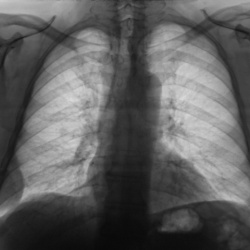

"Бабулька"...Контроль после "флюшки".

29.09.2009 - 22:50